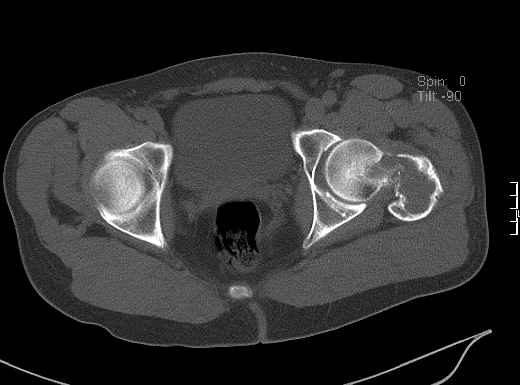

Уважаемые коллеги! Больной (1974 г.р.) травма 26.01.2009г., у пал на ра-боте с высоты своего роста, доставлен в одну из горбольниц Екатеринбурга в травматологическое отделение. На рентгенограмме выявлен патологический перелом чрезвертельной области левого бедра.

Доброкачественная опухоль (ОБК?, энхондрома?), по данным RS. Дополнительно произведено КТ. Наложено скелетное вытяжение.

Прилагаются: рентгенограмма и данные СТ